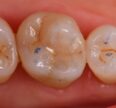

Large Class I Restoration with Amalgam removal

Large Class I core replacement in preparation for a full coverage restoration in due course. #VocoGrandioSO #largeamalgamrestorationremoval